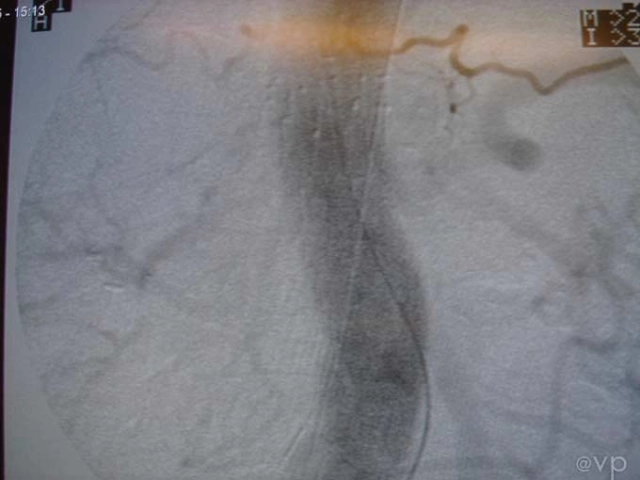

Intestinal

| Hybrid